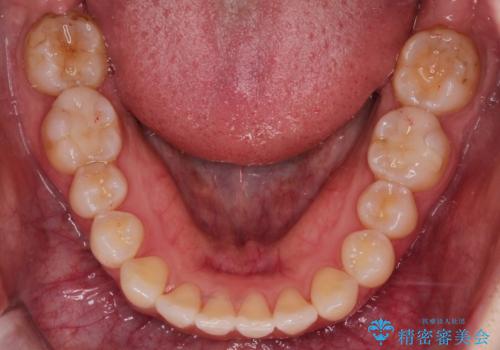

前歯と奥歯のガタガタを矯正で改善

- 患者様は、前歯と奥歯のガタガタ(叢生)を改善し、正面から見た時の歯並びを美しく整えたいとのご要望で来院されました。診断の結果、非抜歯での矯正が可能と判断し、インビザラインを使用する治療計画を立案しました。透明な矯正装置で目立ちにくい治療を行いながら、前歯と奥歯の両方を整列させることを目標にしました。

インビザラインを用いて、前歯の見た目を重視しつつ、奥歯のガタガタも改善しました。特に正面から見た際の美しい歯列を意識し、段階的に歯を移動させることで、全体の調和を図りました。治療中は、適切な装着時間を守ることや、装置の清潔を保つことが重要でした。また、歯肉や歯列全体に無理な負担がかからないように移動を管理しながら治療を進めました。結果として、前歯と奥歯がきれいに並び、見た目にも機能的にも満足いただける仕上がりとなりました。